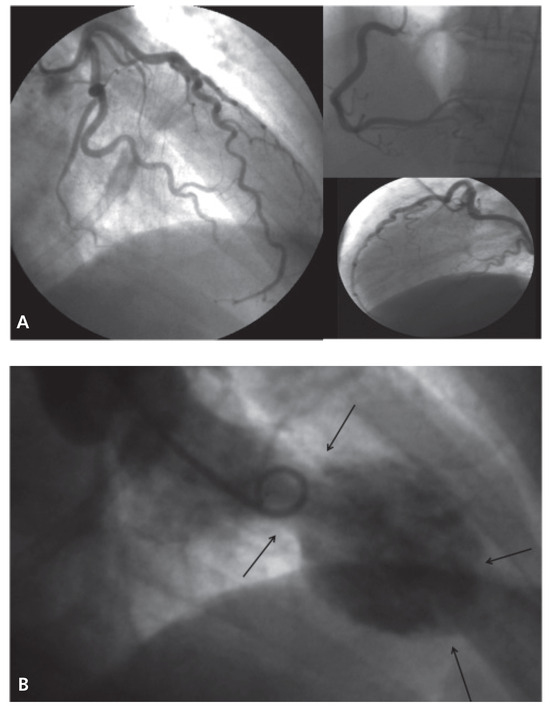

Heart Failure in a Patient with Multi-Organ Sarcoidosis

by Marc Buser, Theresa Dellas Buser, Jens Bremerich and Daniel Tobler

Cardiovasc. Med. 2012, 15(11), 329; https://doi.org/10.4414/cvm.2012.00124 - 21 Nov 2012

A 53-year-old woman was admitted to our emergency department with progressive shortness of breath during exertion for three months. [...] Full article

Figure 1